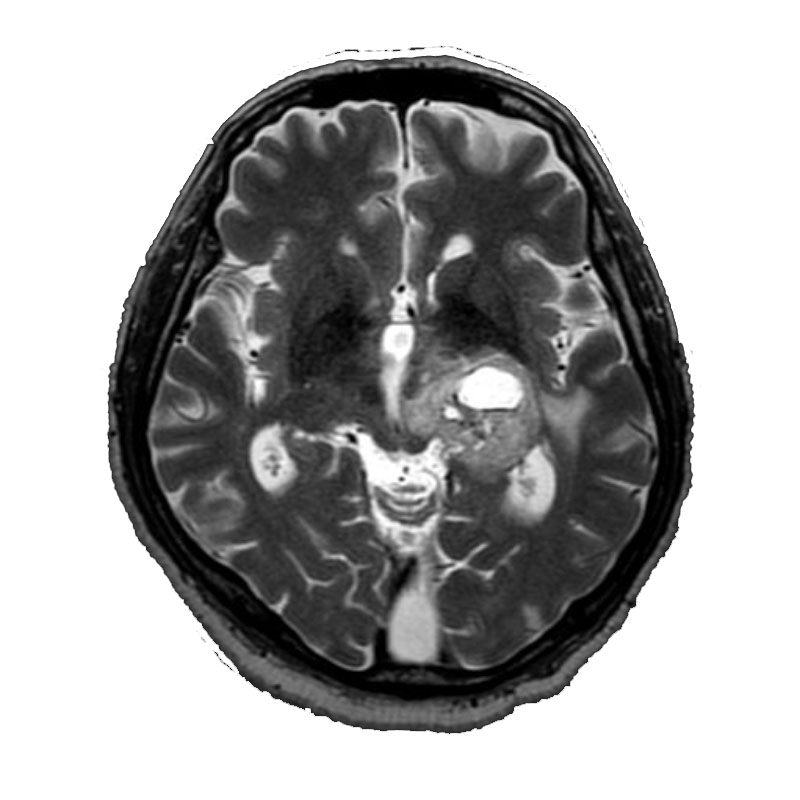

脳動脈瘤(Rt.IC-PC)

フローダイバーター留置術

芝野/古谷/木本

脳動脈瘤(Lt.IC-PC)